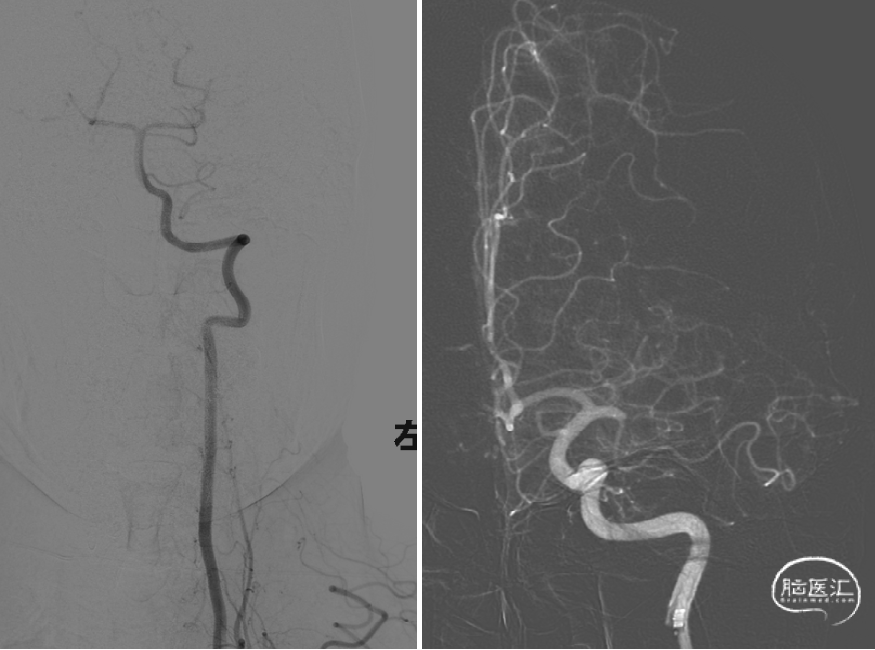

将6F 132cm Cat 6中间导管送至左侧颈内动脉末端,将Synchro微导丝及取栓支架微导管通过闭塞段血管,经微导管造影提示进入血管真腔,引入Trevo ProVue 4*20mm取栓支架,精确定位后缓慢回撤微导管释放取栓支架覆盖闭塞段血管,远端血流即刻恢复,等待5分钟血栓与支架充分嵌合,关闭灌注系统,注射器持续负压抽吸中间导管,将中间导管跟进至取栓支架近端,将取栓支架及中间导管整体撤出体外,支架内可见少许碎屑样血栓。

复查造影显示左侧大脑中动脉显影良好,M1段局部毛糙,前向血流:TICI分级:III级,予以替罗非班5ml动脉内缓慢推注,观察15分钟、30分钟分别造影,左侧大脑中动脉显影良好,考虑患者年轻,未放置支架。